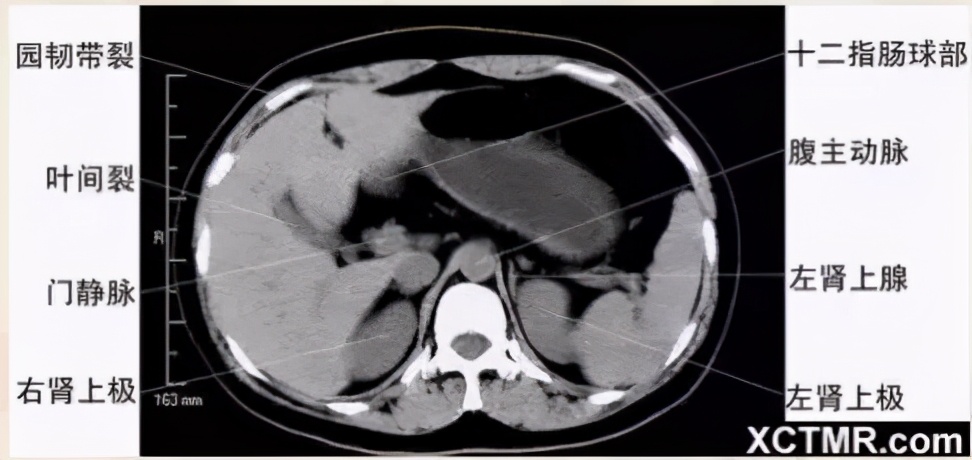

腹部CT